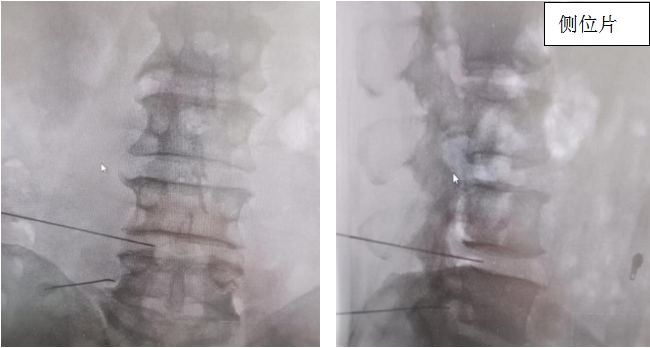

术中穿刺定位:

通过一个半小时的精细操作,手术顺利完成,术后患者即感腰部及左下肢疼痛明显减轻,直腿抬高达到50°,经过一周治疗,田大叔已经能正常行走,并对疗效非常满意。